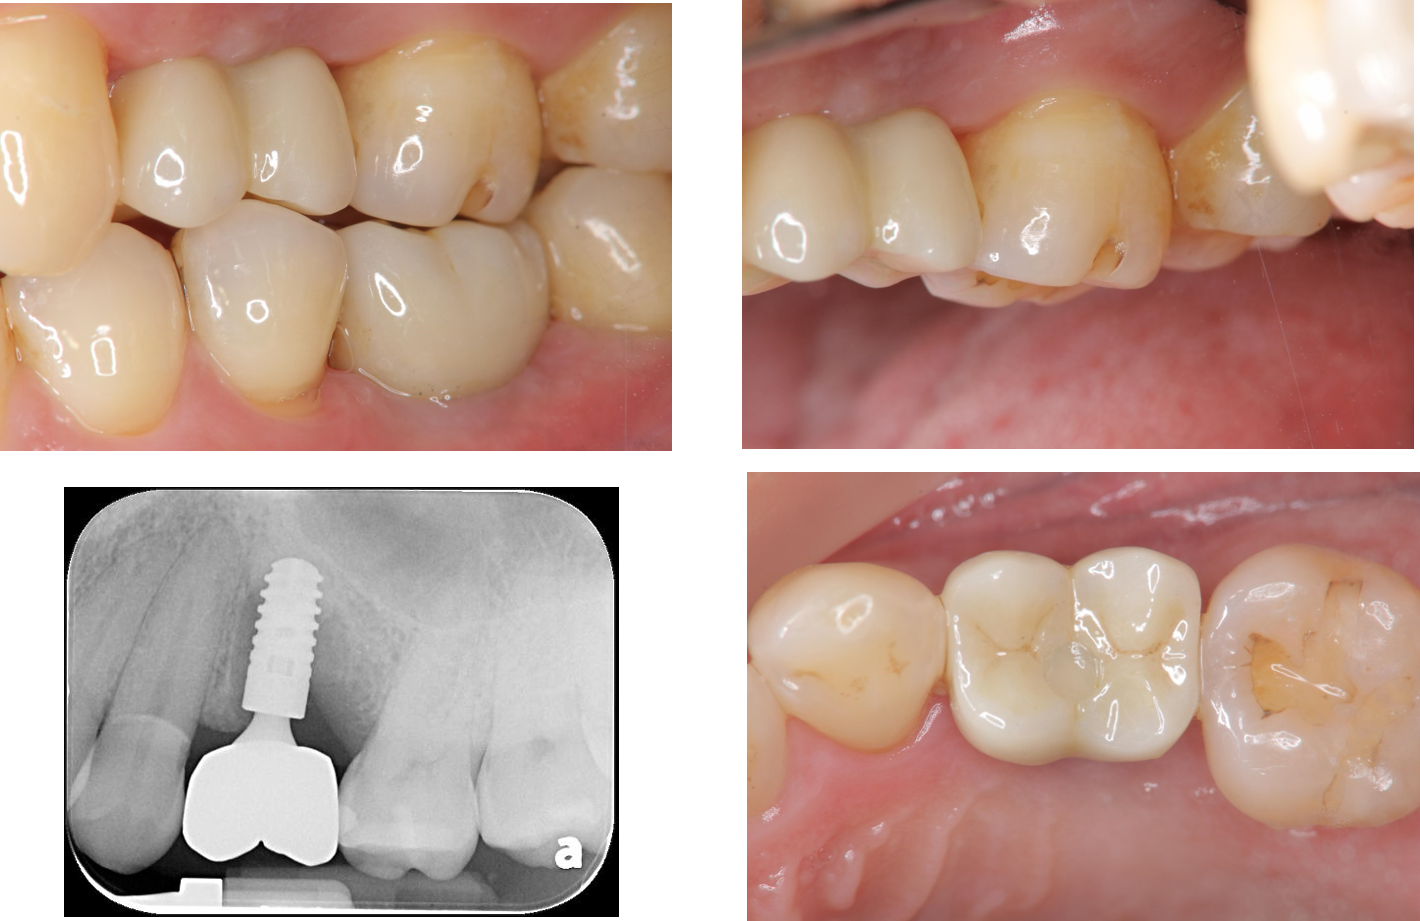

螺絲固定式膺復物

治療後,上顎植牙口內適應良好

治療後,下顎植牙口內適應良好